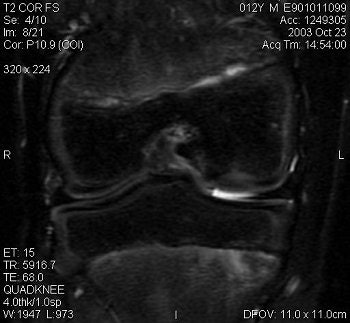

![]() |

| Above and below, OCD of the medial femoral condyle in a female child. Images courtesy of Dr. Douglas Beall. |

JOCD that involves "a large portion of the medial femoral condyle of the knee can be tremendously debilitating," Beall said. "We see anything from a casual bruise all the way to a loose osteochondral fragment. Often we'll see OCD that involves only the cartilage, all the way through a little bit of the underlying bone. A lot of times they'll heal; sometimes the cartilage will fissure; sometimes the underlying bone is damaged. Fluid from the joint can get in between the cartilage and the bone," resulting in severe osteochondritis.